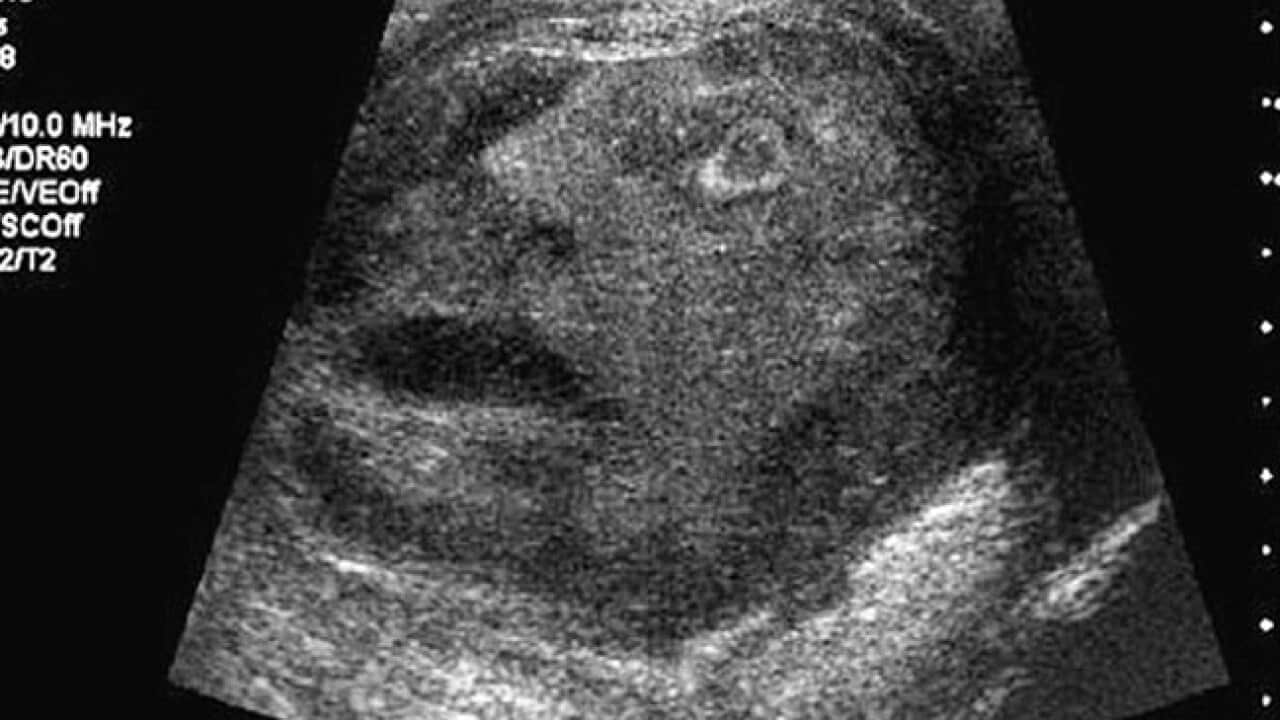

Two years ago, doctors at a teaching hospital affiliated with Queen's University in Kingston, Ontario, spotted what appeared to be a face in ultrasound images of a 45-year-old patient's scrotum.

"While scrolling through the ultrasound images, the residents and staff alike were amazed to see the outline of a man's face staring up out of the image, his mouth agape as if the face seen on the ultrasound scan itself was also experiencing severe (pain)," doctors Gregory Roberts and Naji Touma wrote in the journal Urology.

"A brief debate ensued on whether the image could have been a sign from a deity (perhaps Min the Egyptian god of male virility); however, the consensus deemed it a mere coincidental occurrence rather than a divine proclamation."

The discovery was published in the latest issue of the journal Urology under the banner "The Face of Testicular Pain: A Surprising Ultrasound Finding."